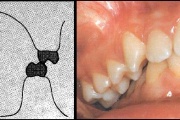

) Röntgenülesvõte. Ülemise esimese jäävmolaari lõikumine on takistatud 2. piimamolaari tõttu

Esimese jäävmolaari ektoopiline lõikumine